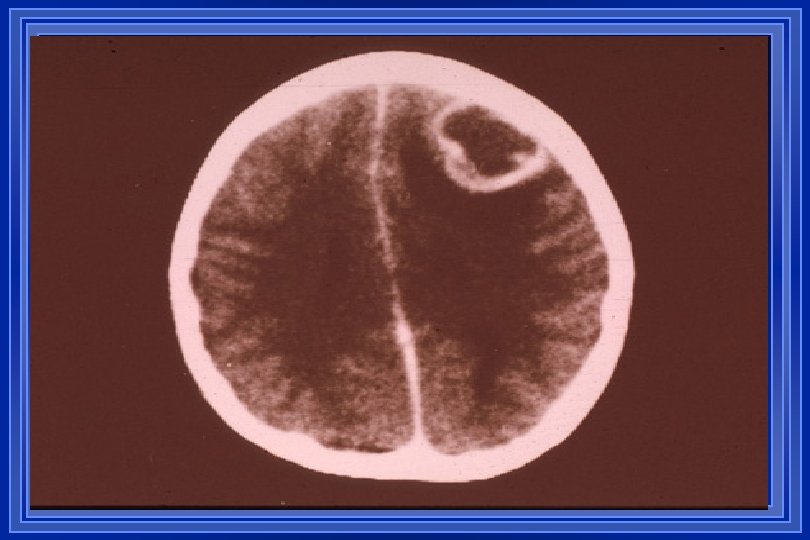

BRAIN ABSCESS l l l l Infrequent but not uncommon; pathogenesis diverse with contiguous spread & blood-borne seeding most common Clinical features include HA (90%), fever (57%), MS changes (67%), hemiparesis (61%), & papilledema (56%) Dx often suggested by neuroimaging (CT or MRI) LP is contraindicated due to risk of herniation Infxns often polymicrobial (strep, enteric GNRs, &/or anaerobes); S. aureus may cause abscesses in association with IE Other less common etiologies include Nocardia, fungi, M. tuberculosis, T. gondii, & neurocysticercosis Drainage often a necessary component of management

Multiple abscesses in a 6 -yearold child